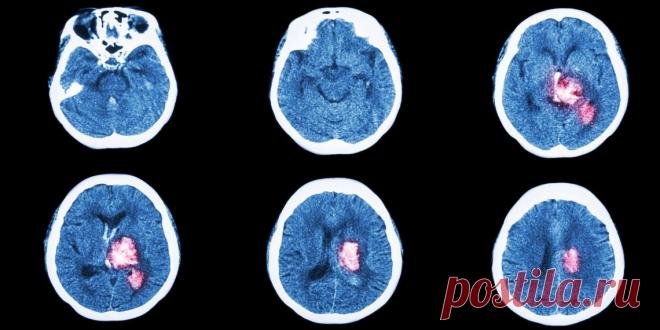

6 признаков инсульта, при которых нужно действовать как можно быстрее

У врачей есть несколько часов, чтобы спасти человека. Симптомы инсульта нужно знать всем, чтобы успеть распознать болезнь.